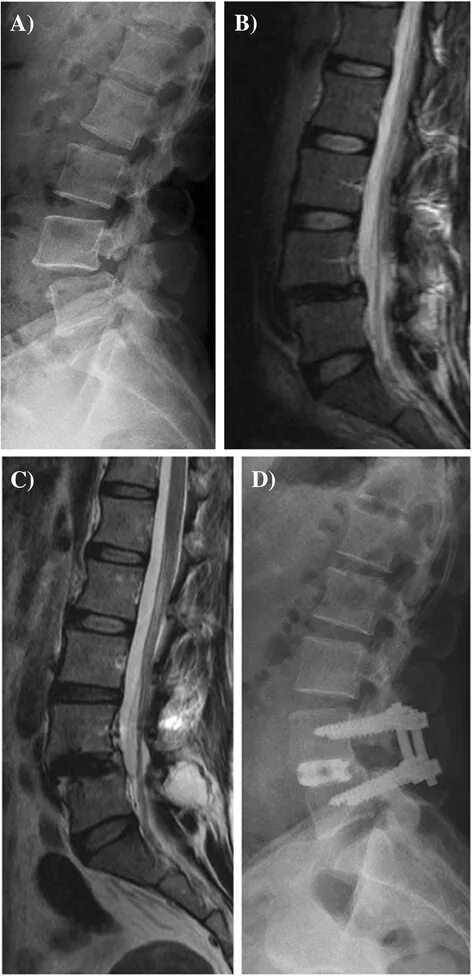

L 4 s1